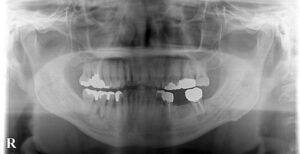

🔶オペ前レントゲン🔶

下の奥歯は初診の段階で

良くない歯が何本かありましたが

自覚症状が無かったので矯正開始